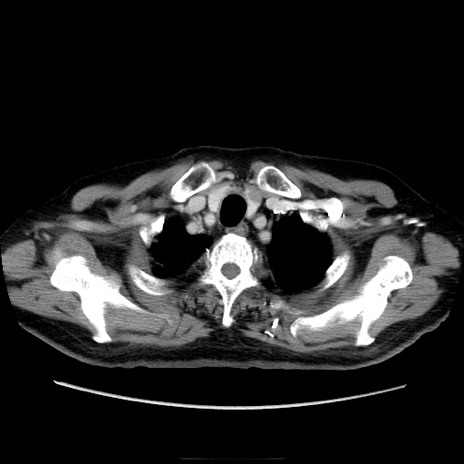

症例21(横断像)

【症例】70歳代男性

【主訴】腹痛

【現病歴】肝硬変・肝細胞癌にてかかりつけの方。約9時間前に食後より腹痛出現。症状が徐々に増悪し、嘔吐出現したため来院。

【既往歴】肝硬変、肝細胞癌(RFA、TACE後)

【身体所見】意識清明、表情苦悶様、BT 36℃、BP 129/78mmHg、P 88bpm、SpO2 97%(RA)、右上腹部から心窩部にかけて圧痛あり、反跳痛なし、筋性防御あり。

【データ】WBC 5800、CRP 0.16